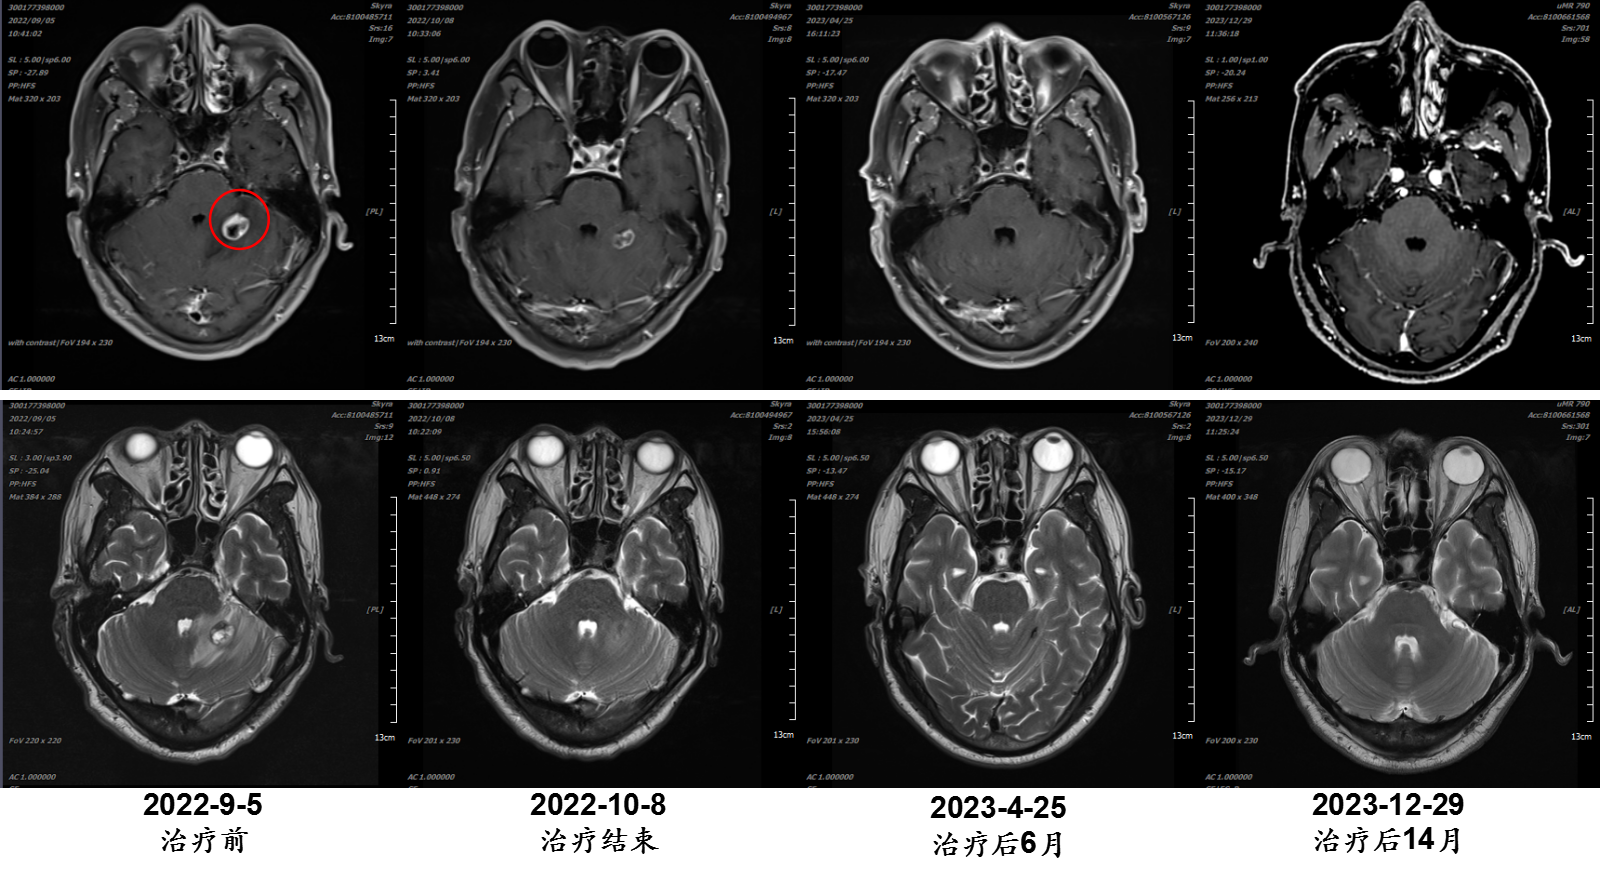

张某某,男,57岁;诊断:食管癌多发脑转移;治疗时间:2022/9/20至2022/10/7。

病例提供医生:王馨 科室:放疗中心一科(国际一部)